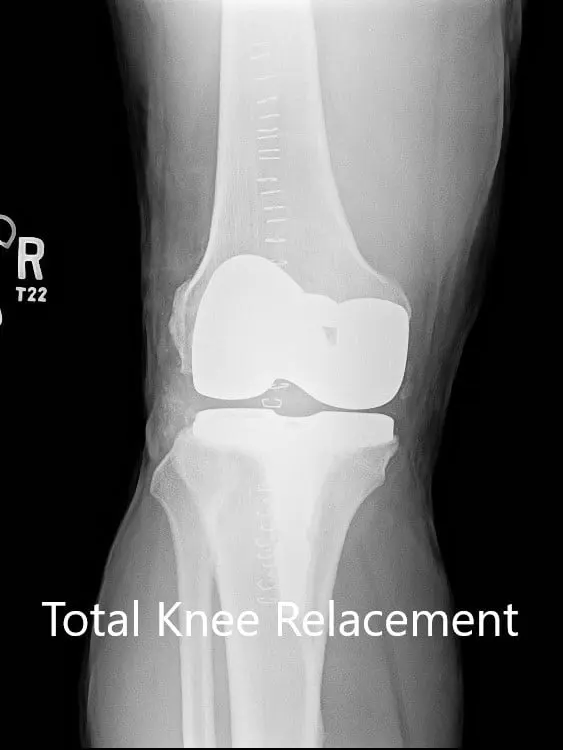

IMPLANTS USED: Posterior stabilized femur size 11 with tibia size F with a tapered stem with 12-mm constrained posterior stabilized polyethylene.

Postoperative X-ray of the right knee with a prosthesis in anteroposterior and lateral views.